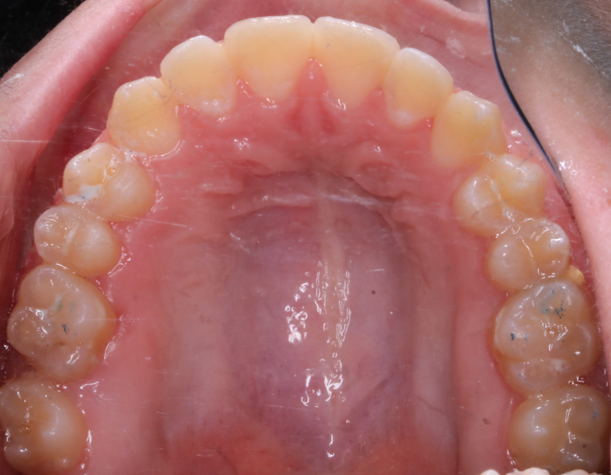

Llama la atención a primera vista la mordida abierta bilateral, especialmente pronunciada entre el cuadrante 1 y 4 debido a una interposición lingual en posición estática. Entre otros hallazgos fundamentales, observamos: un patrón dolicofacial severo (VERT: -2), una compresión de la arcada superior que cursa con un perfil y relación oclusal de clase III y la rotación del 35 y 45. Este caso se trató con un disyuntor, exodoncias de 44 y 34, brackets convencionales y educadores para rehabilitación de la lengua en un tiempo de 22 meses. Aunque estoy satisfecho con el resultado final, me hubiera gustado clavar la interscuspidación de premolares en el cuadrante I y IV, y mejorar la relación oclusal de cuadrante II y III. Sin embargo, lo bonito, es que hay a veces, en la ortodoncia real, que el paciente está satisfecho y quiere terminar antes de tiempo, o por el contrario, que el profesional intenta pero no consigue el resultado deseado. Y a mí más que compartir casos perfectos, me gusta mostrar mis errores, mi realidad.

La ilustración nos deja entrever algo tan fácil como que en un paladar pequeño no entra una lengua grande. Y viceversa, en un paladar grande entra una lengua grande. Llevándonos dicha explicación al caso que nos atañe, podemos ver  en la fotografía lateral del lado derecho como la lengua escapa y busca espacio, de manera permanente, entre el cuadrante 1 y 4,  estímulo que mantenido en el tiempo generó en una mordida abierta lateral.

-Antes de rehabilitar la función, es mejor tratar la forma. Lo que quiero decir que bajo mi punto de vista, en esta paciente, no tenía ningún sentido realizar el trabajo funcional de la lengua, sin previamente haber realizado una disyunción del maxilar superior.